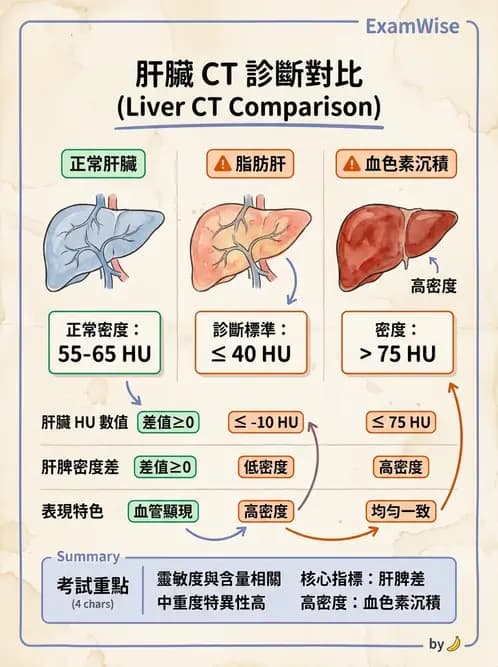

未注射對比劑(unenhanced)CT 判讀肝臟密度異常的基本原則:正常肝臟 Hounsfield unit(HU)約 55–65 HU,高於脾臟(~40 HU),因此正常肝臟在 CT 上應比脾臟更亮(高密度)。當肝臟出現脂肪浸潤,三酸甘油脂取代正常肝細胞,HU 下降,肝臟相對脾臟呈低密度(hypodense),即為脂肪肝(fatty liver / hepatic steatosis)的典型表現。

定量標準:Unenhanced CT 診斷脂肪肝的切斷值為:

- 肝臟絕對 HU ≤ 40 HU,或

- 肝脾 HU 差值